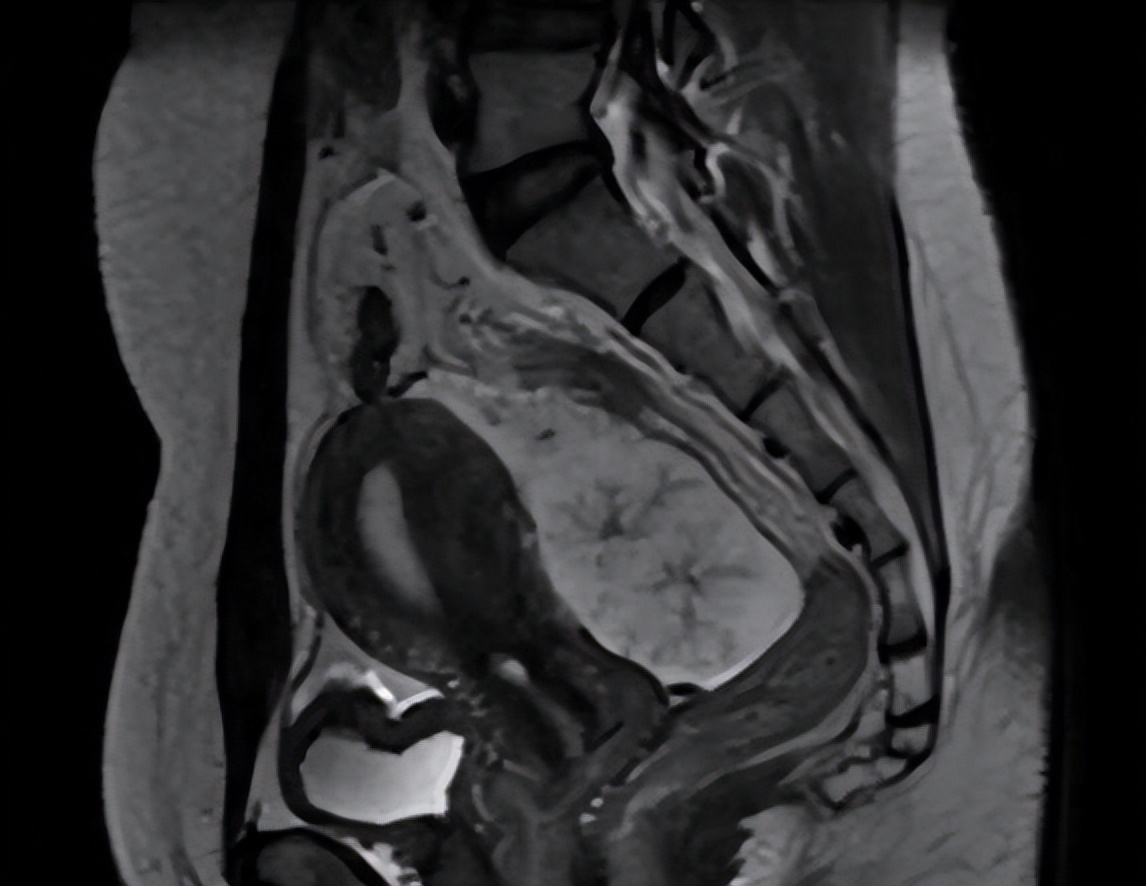

术前MR图像

术后化疗后MR图像